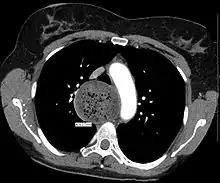

![]() | |

| A chest X-ray showing achalasia (arrows point to the outline of the massively dilated esophagus) | |